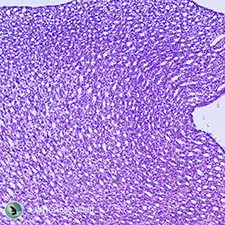

| Kidney l.s. | Liver | |